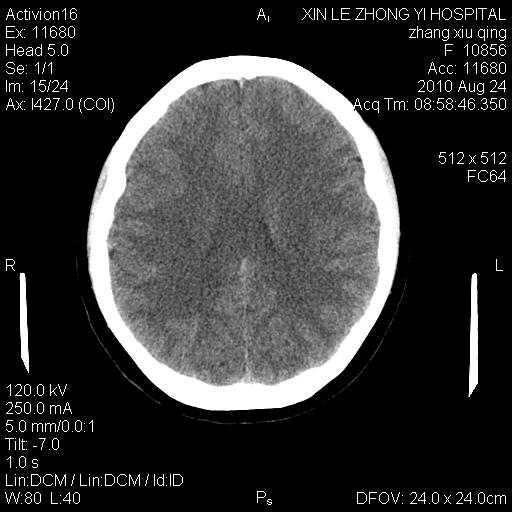

标题: CT28569:看看鞍上池正常吗

女 24 偶有头晕

未见明显异常,必要时可作mri

没什么!只是扫描层面与听眦线不平行

伪影干扰下,所见无水肿、无占位,建议定期复查。